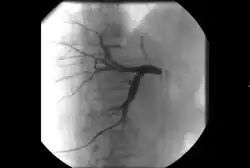

• Cholangiography: Imaging the bile ducts within the liver to look for areas of blockage.

Biliary intervention

In addition to normal liver tissue, the liver has three main vessels traversing it: arteries, veins and bile ducts. While bile is made in the liver and stored in the gallbladder, the bile eventually passes into the GI tract through the hepatic, cystic and common bile ducts. Any condition that prevents the normal flow of bile from the liver, through these bile vessels and into the GI tract can cause a condition called jaundice.

While jaundice can be caused by a few viruses that the human body can naturally clear, jaundice in the setting of an obstruction is usually caused by a cancer and can result in intolerable itching and a worsening of liver function that can be life-threatening. Depending on a patient's condition, this type of obstructive jaundice can be alleviated with surgery or chemotherapy but if these measures fail to restore proper flow of bile, an interventional radiologist can perform a procedure called a percutaneous transhepatic cholangiography (PTC).[21]

A PTC is an outpatient procedure lasting anywhere from 15 minutes to an hour where an interventional radiologist accesses the patient's bile duct system with a needle through the skin and liver under imaging guidance. Using fluoroscopy (essentially an X-ray camera) to guide a wire (followed by a catheter over the wire) through the bile duct system and into the GI tract, essentially restoring the normal flow of bile. If the patient's GI tract cannot be accessed due to the obstruction, the catheter can be placed to drain the bile duct system into a bag that the patient can wear during daily activities. Risks of this procedure include bleeding and infection but these are much lower than an equivalent surgical procedure.[21]